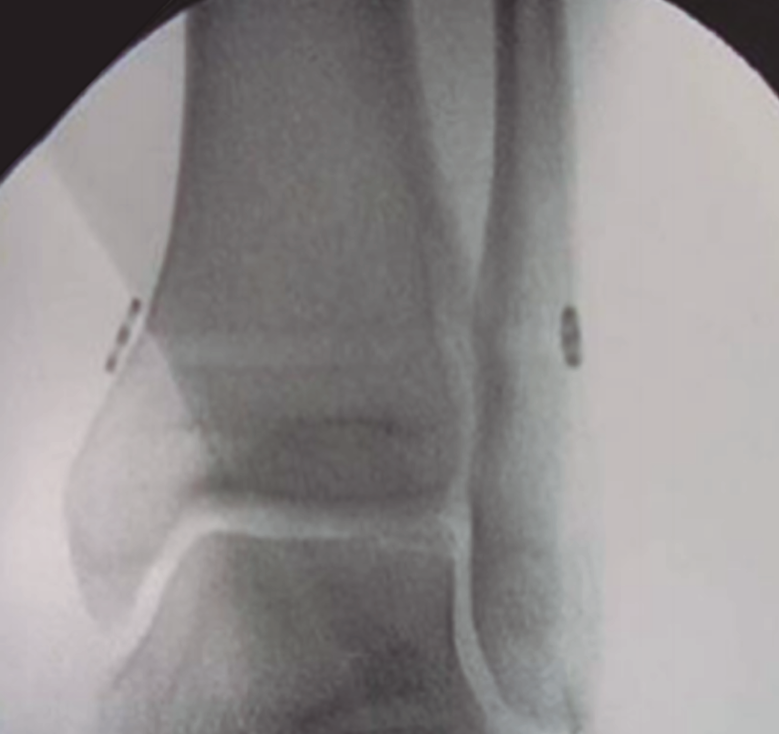

Para evitar problemas asociados con los tornillos, se crean los métodos de fijación elásticos, siendo una buena alternativa desde finales de la década de 1990. Son técnicas más fisiológicas y se adaptan mejor a la dinámica de la sindesmosis. Algunos estudios biomecánicos han descrito que aportan menos reducción que los tornillos y, por tanto, es aconsejable darle tensión al sistema con el tobillo en flexión plantar parcial, permitiendo un mayor ajuste y cierre de la mortaja. La posición del implante es la misma que para los tornillos. Se permite la carga completa a las 2 o 3 semanas. Hasta la fecha, para lesiones aisladas de las sindesmosis inestables, ningún estudio ha demostrado que las técnicas de fijación dinámicas sean inferiores a la fijación rígida con respecto a la estabilidad y la satisfacción del paciente. Los beneficios más notables de esta técnica son evitar un segundo procedimiento quirúrgico para la extracción de los tornillos, la carga más precoz y una menor alteración biomecánica (Figura 4).

Figura 4. Fijación dinámica con botón de sutura.